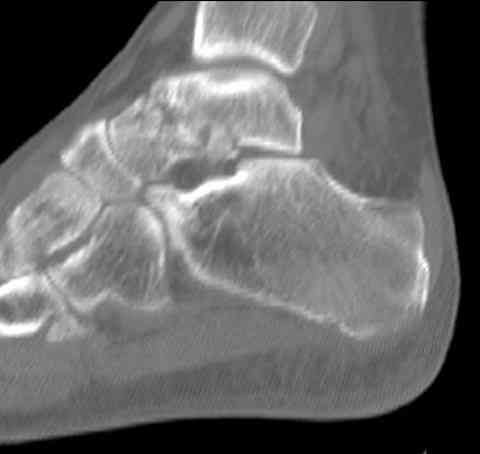

а основании двух видов ренгенограмм невозможно радикально решить о необходимости открытой репозиции или первичного артродеза.

Для оценки состояния нужны дополнительные исследования, например Canale или Broden ренгенограммы и Компьютерная томография.

При переломах тарана всегда имеется риск AVN, а классификация Hawkins поможет разобраться с предполагаемыми осложнениями.

Если в первом типе, когда перелом шейки без смещения, тогда AVN менее 10%, при втором типе когда имеется смещение и вывих тарана в субталарном сочленении меньше 40%, а при типе III когда смещение в голеностопном и субталарном суставах - около 90% и в типе IV, когда происходит полный вывих, риск AVN достигает 100%.

Для оценки состояния нужны дополнительные исследования, например

> Canale или Broden ренгенограммы

повторили рентгенограммы и доделали проекции, к единому мнению все еще не пришли

На ренгенограмме не уловил многоскольчатость тарана, чтобы доказать, конечно, можно было исследовать на КТ, потом КТ дает ориентацию фрагментов.

Два фрагмента суставной поверхности тарана можно восстановить боковой компрессией шурупами и дополнительно костная пластика.